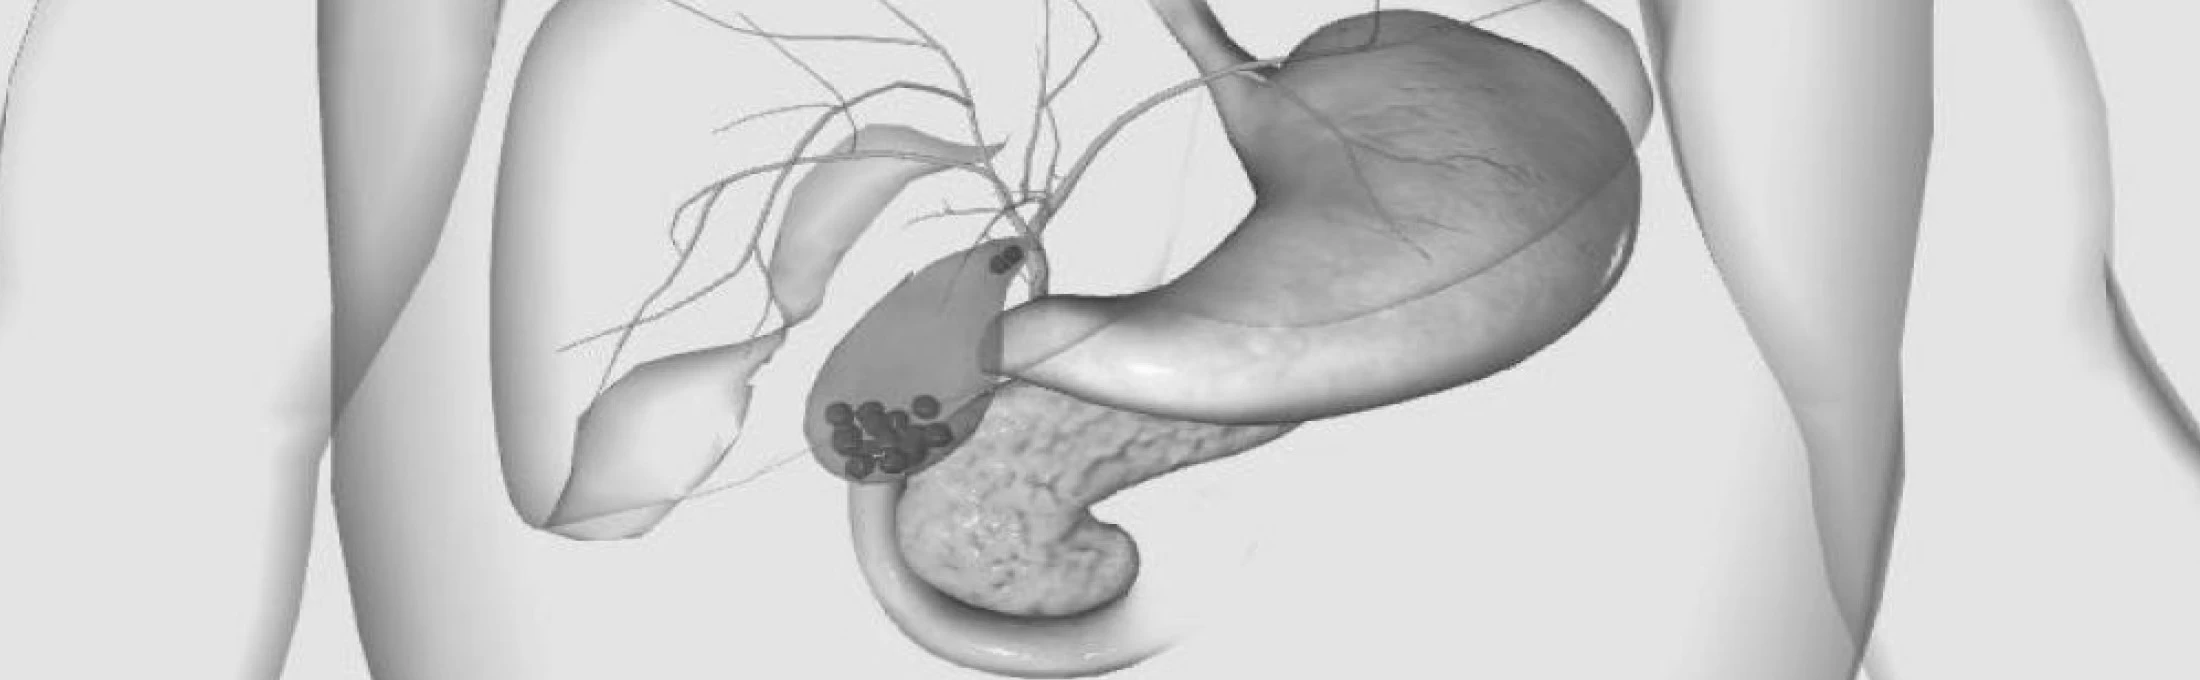

Анатомия и особенности Гартманова кармана желчного пузыря